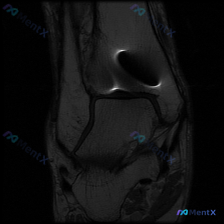

刚整理了一个很有临床意义的病例,核心矛盾是「临床怀疑软骨异常,但现有影像完全正常」,把整个分析思路分享给大家。 病例基础信息 这是一份单张膝关节矢状位T1加权MRI影像,临床提出的核心观察方向是「软骨异常」,无其他临床病史、症状或其他检查资料。 影像具体观察结果 我们先把影像所见说清楚: 1. 骨骼...

看到这个病例挺有代表性的,整理出来和大家分享一下思路。 病例基础信息 这是一张膝关节矢状位T1加权序列MRI影像,用户提出问题:观察图像是否存在软骨异常。 先给大家整理影像评估的基本结果: 1. 骨骼结构:股骨远端、胫骨近端、髌骨皮质连续,骨髓信号未见异常高低信号,关节面形态基本正常 2. 半月板:...

今天整理了一个很有启发意义的读片病例,问题是临床怀疑膝关节软骨异常,只给了一张矢状位T1加权MRI,我们一起来梳理整个分析过程。 病例影像基础信息 这是一张膝关节矢状位T1加权像(T1WI),我们先把基础解剖评估说清楚: 1. 骨骼结构:股骨远端、胫骨近端骨皮质连续,无骨质破坏或骨折,关节间隙正常,...

病例基础信息 这是一份特殊的膝关节影像评估需求:输入描述提示存在软骨异常 (Chondral abnormality),提供1张膝关节矢状位MRI静态图像,我们先看影像学分析结果: 影像学观察结果 1. 骨骼与软骨:股骨远端、胫骨近端、髌骨骨皮质完整,无骨折,无骨髓水肿;股骨髁、胫骨平台、髌股关节面...

病例读片讨论:怀疑软骨异常,单张MRI却没发现问题,该怎么办? 这是一份膝关节矢状位T1加权MRI读片需求,核心疑问是排查软骨异常,我整理了完整的分析思路分享给大家。 一、影像基础信息 本次读片仅提供单张膝关节矢状位T1加权MRI图像: - T1序列中,骨髓脂肪呈高信号,液体、皮质骨、半月板等致密组...

拿到这个病例:核心问题是「这张膝关节MRI里的软骨异常在哪里?」,先把读片结果和思路整理给大家。 一、先整理读片基本信息 这是一张单张膝关节矢状位MRI,信号对比度提示更符合质子密度加权像(PDWI)或T2加权像(T2WI),不是典型T1加权像,层面在膝关节中线附近,可以清晰显示后交叉韧带。 逐结构...